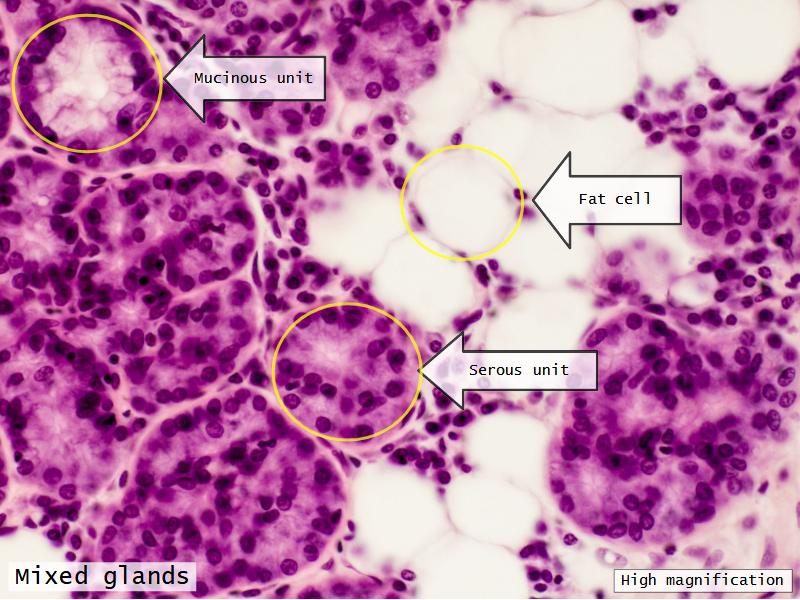

Trachea

Bronchi - Transitions

- Intrapulmonary bronchi

- Irregular cartilage

- Respiratory epithelium

- Glands

- Bronchioles

- NO glands - goblet cells -> secretory cells